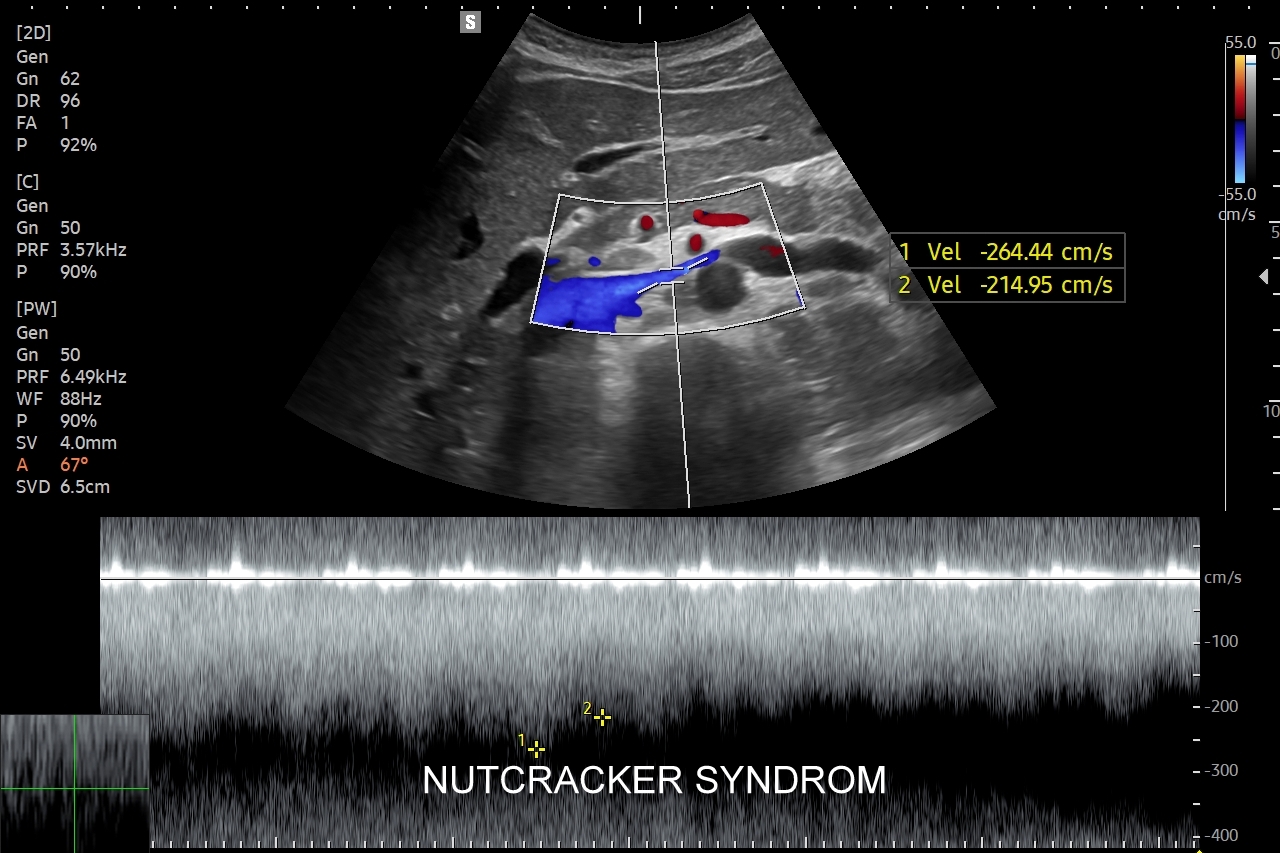

Inne wskazania do przeprowadzenia diagnostyki USG przepływów nerkowych obejmują ocenę funkcji nerek w przebiegu chorób ostrych oraz przewlekłych, takich jak nefropatia cukrzycowa, glomerulopatie, czy zapalenia kłębuszków nerkowych. Badanie USG Doppler wykonywane jest również przy podejrzeniu zakrzepicy żyły nerkowej i zespołu „dziadka do orzechów”; przy stwierdzeniu obecności żylaków powrózka nasiennego u mężczyzn; żylaków miednicy u kobiet; w sytuacjach, gdy podczas standardowego badania USG jamy brzusznej uwidoczniono patologię nerki (np. guz nerki, marskość); a także przy stwierdzeniu podwyższonych wartości parametrów nerkowych w badaniach laboratoryjnych (kreatynina, mocznik, cystatyna C, potas) oraz w ramach oceny USG nerki przeszczepionej.